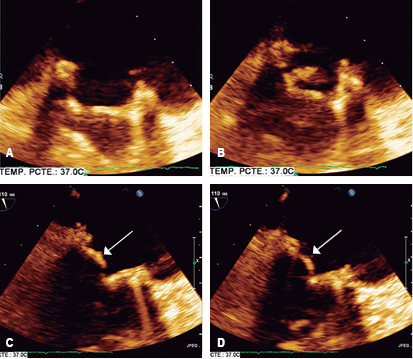

Transthoracic and transesophageal echocardiography: left ventricular end-diastolic volume of 45 milliliters, systolic volume of 11 milliliters, ejection fraction 76%, without changes in global or segmental mobility at rest, without thrombi, with concentric remodeling data; dilated left atrium without thrombi, a left atrial volume index (LAVI) 48 mL/m2 is calculated; mitral valve bio-prosthesis thickened, heavily calcified, irregular by pannus (Figure 3), with inadequate excursion and closure, with one of the leaflets fixed (Figure 4), an acceleration of flow rate 2.9 m/s, it shows maximum peak velocity of 2.9 m/s with maximum gradient of 34 mmHg and mean gradient of 25 mmHg (Figure 5), valve area by continuity 0.5 cm2, indexed 0.3 cm/m2, by pressure half-time of 0.7 cm2, with mild central regurgitation jet, Doppler index of 4; aortic valve bio-prosthesis with mild calcification, with suitable excursion and closing, maximum peak velocity of 2.2 m/s, maximum gradient 29 mmHg, mean gradient 15 mmHg, valve area by continuity 1.3 cm2, indexed 0.81 cm/m2, with no evidence of leakage, a Doppler index of 0.28; right ventricle: dilated, hypertrophic, with preserved systolic function, tricuspid annular plane systolic excursion (TAPSE) 17 mm/m2, S wave 12 cm/s; right atrium: dilated, without thrombi; tricuspid valve: structurally normal, deficient coaptation, with a concentric regurgitation jet generating severe failure, vena contracta 10 mm, regurgitation area 16 cm2, a systolic pulmonary artery pressure (SPAP) of 105 mmHg is calculated.

Figure 3: Transesophageal echocardiogram with three-dimensional reconstruction of the mitral bio-prosthesis Carpentier-Edwards #27 (Edwards Lifesciences), degenerated, seen from the left atrium.

Figure 4: Transesophageal echocardiogram: showing the null mobility of the posterior leaflet (arrows), determining an incomplete opening in diastole (A and C). In systole the mitral prosthesis shows significant thickening of one of its valves (B and D).